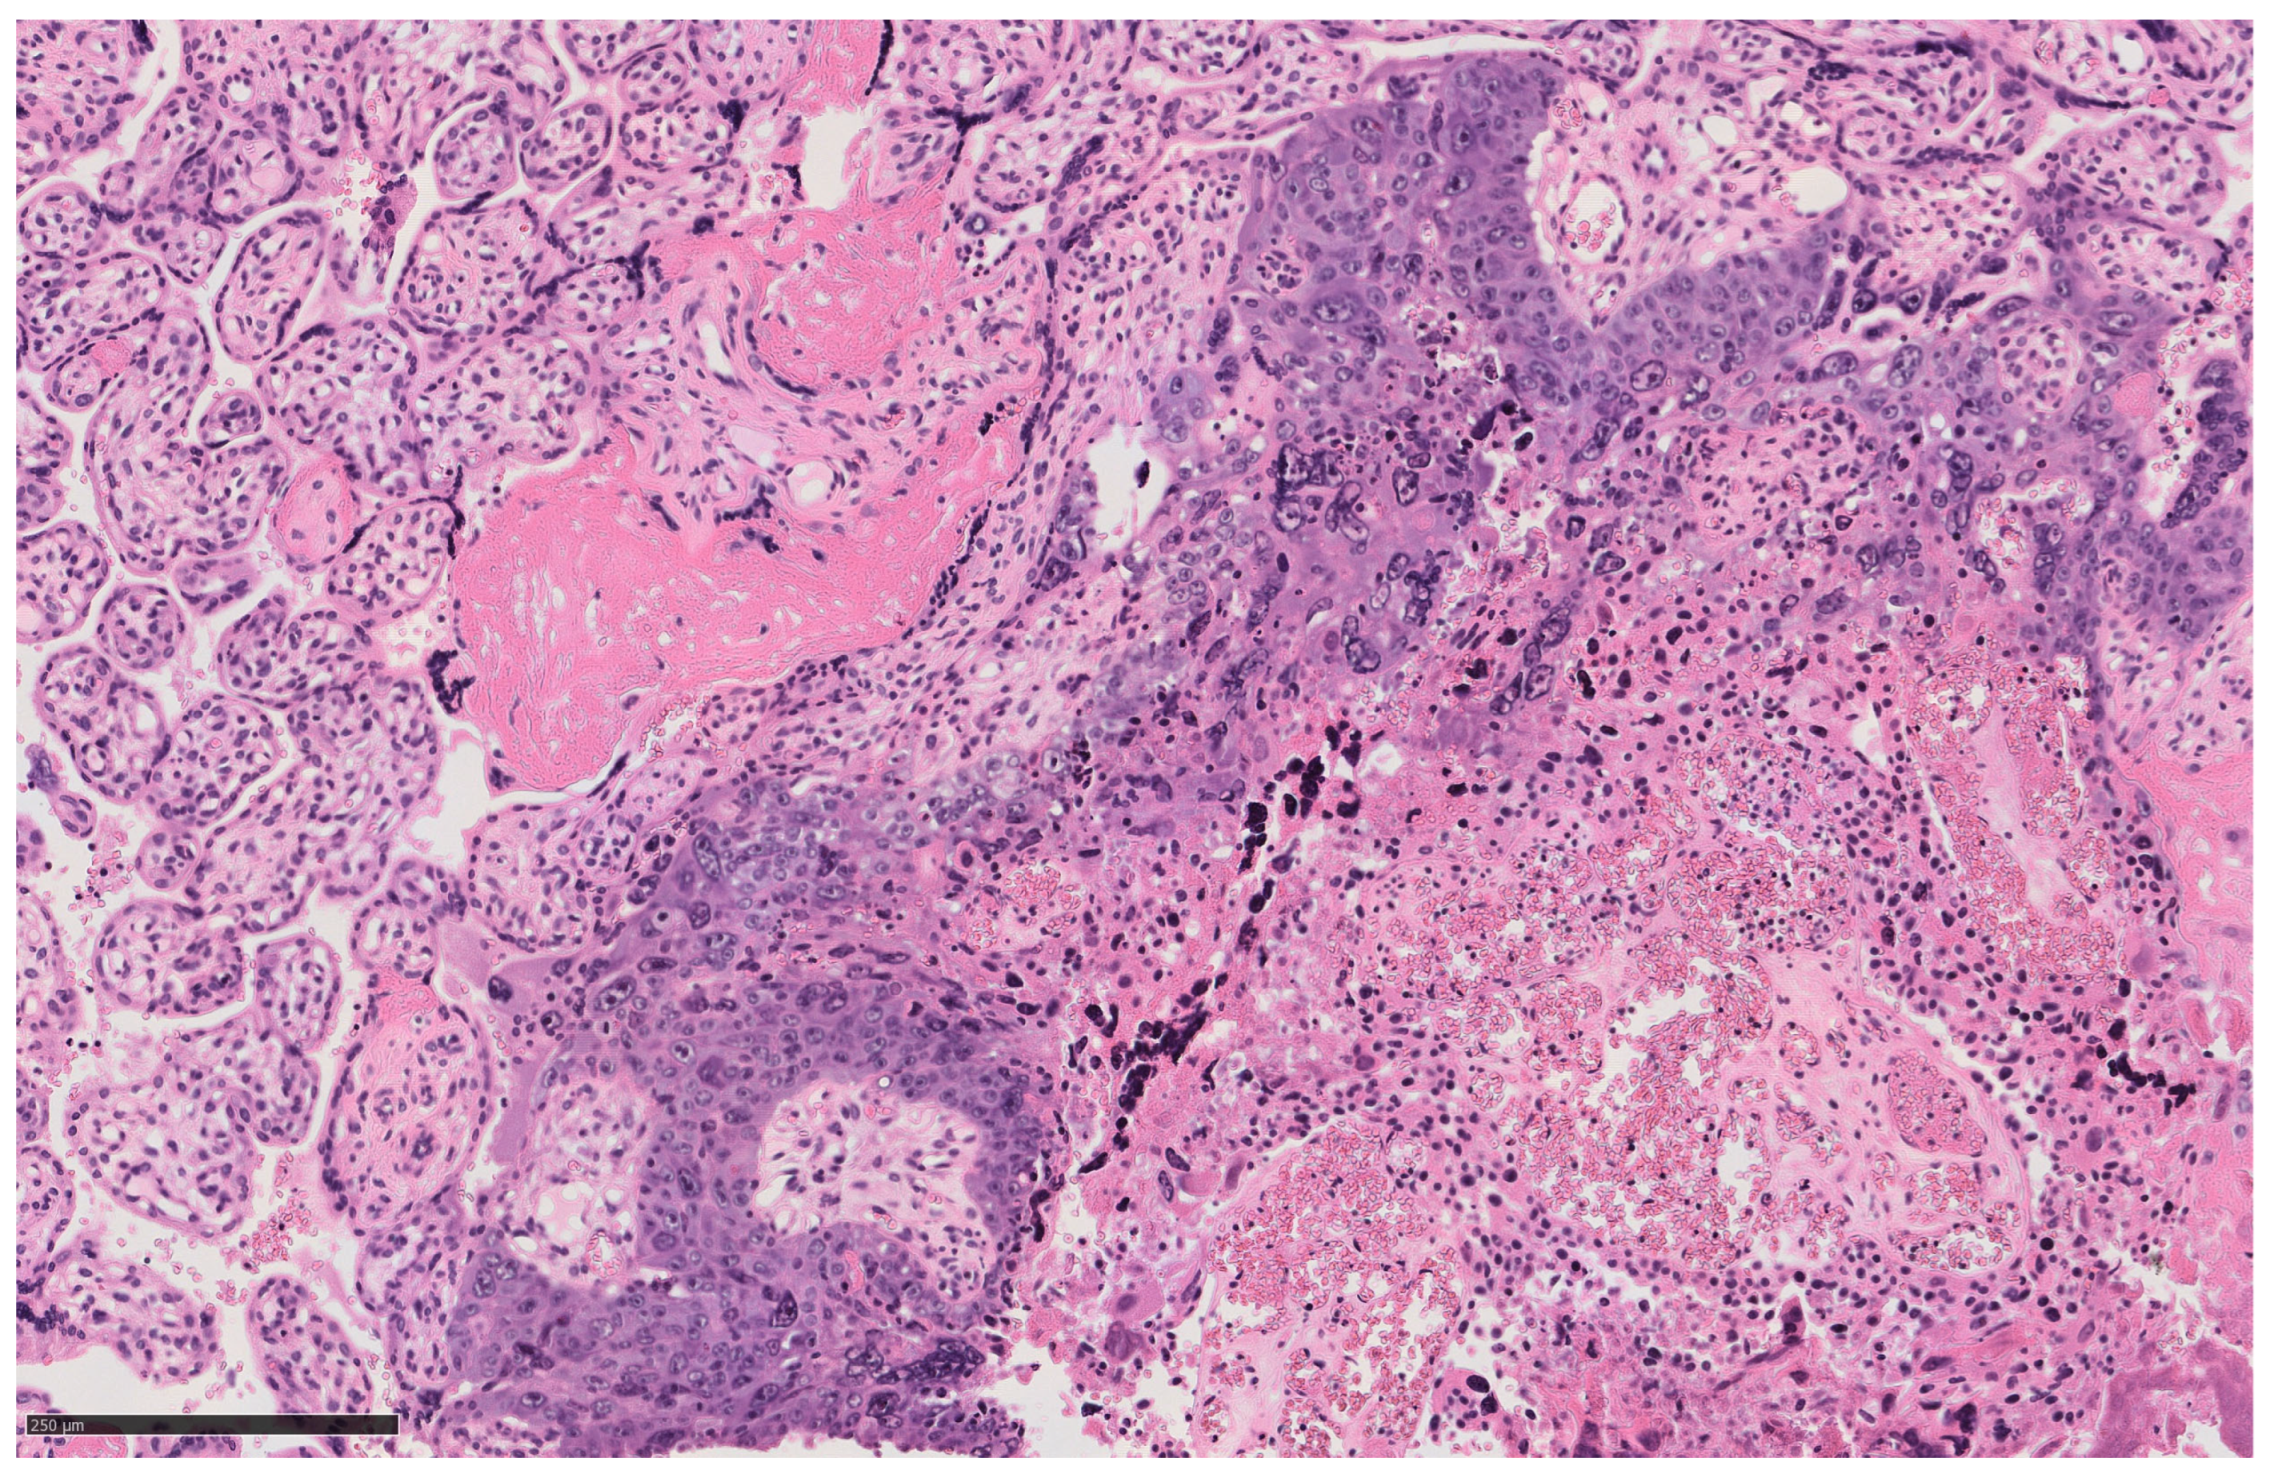

2. Case Description